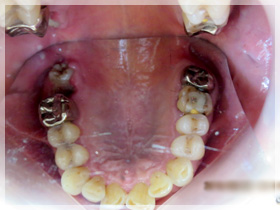

40代女性

ちゃんと噛めない、歯が弱いから治したい、歯が無いからなんとかしたい、歯を見せて笑いたい、顎が痛い

*上はセラミックのブリッジとワイヤーのないアタッチメントを用いた薄いメタルプレー と(金属の入れ歯)に。

*下はセラミックのブリッジを左右にそれぞれ入れる事に。

1:まずは歯周病の治療を徹底的に行い歯をできるだけいい状態にしてから、同時に治療が終わるまでの仮の歯(仮歯)を作り噛める様にしました。上の歯は残せない状態でしたので1本だけ抜歯をしました。

2:上下の仮歯にした状態で、この患者さんに合っているか?を全てのチェックして調整しました。

3:最終的に決めた材料に置き換えました。

ちゃんとなんでも噛める様になったのと、審美的回復にも大変満足していただきました。

口元のハリも出て、唇がちゃんと出てきたと喜んでいただきました。

また顎の痛みもこの頃には無くなりました。良かったです。